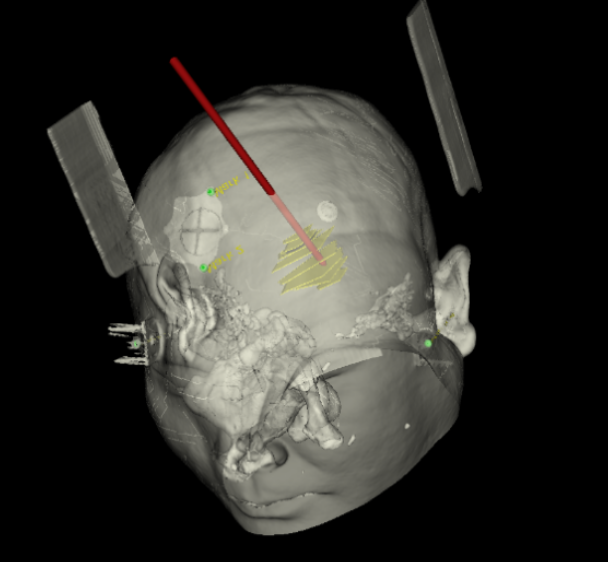

手術(shù)日當天,醫(yī)生團隊通過手術(shù)計劃系統(tǒng)為患者制定手術(shù)靶點及最安全的入顱路徑,隨后將手術(shù)規(guī)劃導入手術(shù)室的機器人當中。

術(shù)前團隊討論手術(shù)規(guī)劃

實際手術(shù)時,機器人在幾分鐘內(nèi)就完成了空間注冊,機械臂在定位儀的引導下自動定位,準確鎖定靶點。

術(shù)前韓帥醫(yī)生使用“睿米”制定手術(shù)規(guī)劃

手術(shù)規(guī)劃在機器人軟件上制定完成